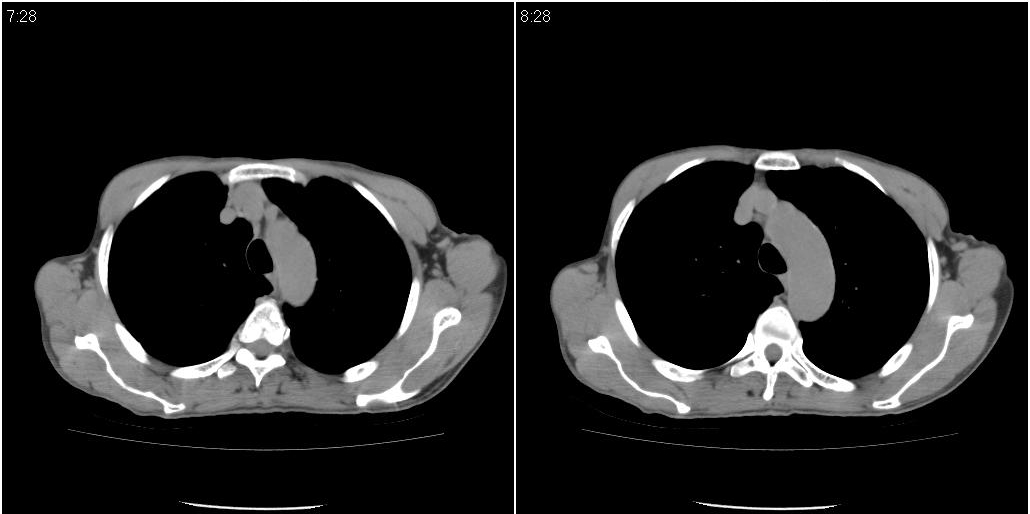

考虑右肺下叶炎症可能性大?未除占位,建议增强。右下肺肺不张

右下肺阻塞性肺炎!建议纤支镜!

标题: ct增强:

右肺中叶阻塞性不张及肺炎,高度怀疑支气管占位,建议纤支镜检查!

1)右肺中叶慢性炎症并支气管扩张,节段性肺不张。2)两肺下叶支气管扩张。